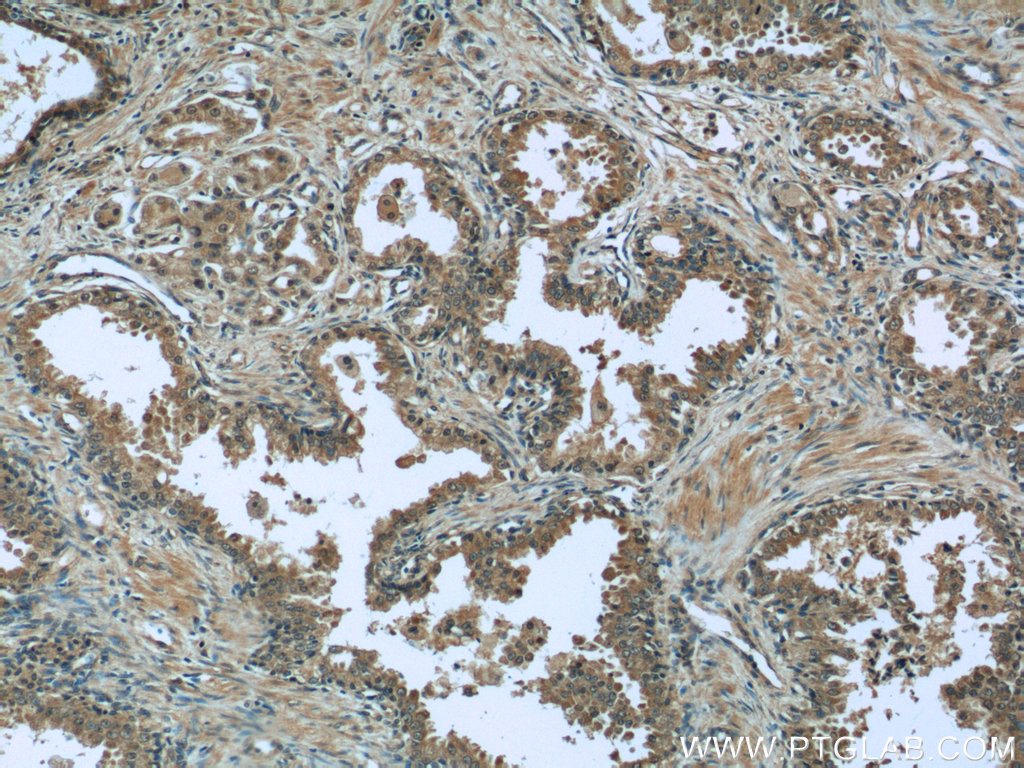

| Positive IHC detected in | human prostate cancer tissue Note: suggested antigen retrieval with TE buffer pH 9.0; (*) Alternatively, antigen retrieval may be performed with citrate buffer pH 6.0 |

| Immunohistochemistry (IHC) | IHC : 1:20-1:200 |